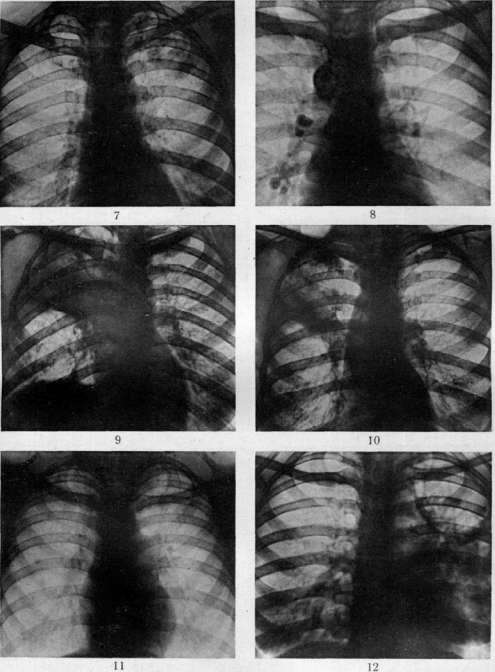

гематогенной генерализацией в результате проникания туб. бацил в ток крови непосредственно или через посредство лимфы (см. Туберкулез). В легких гематогенное поражение проявляется разно. При обшем милиарном Т. в обоих легких наблюдается высыпь массы милиарных туберкулов [см. отд. табл. (ст. 119—120), рис. 3]; в этих случаях ткань легких представляется полнокровной и на таком фоне видны бугорки в зависимости от возраста и типа их или мелкие, серые, полупрозрачные или желтые, с неровными контурами, часто более крупные. Нередко можно, согласно указанию Рибберта (1902), заметить, что у взрослых в верхних районах легких бугорки несколько более крупны, чем в нижних, что объясняют более энергичным ростом туберкулов именно в верхних отделах легких. Если проникание туб. бацил произошло в ветвь легочной артерии, то мидиариза-ция захватывает лишь соответствующую часть легочной территории. Микроскоп, исследование при милиаризации в легких может открыть разный тип бугорков: иногда это типичные продуктивные эпителиоидные бугорки, имеющие своим источником развития альвеолярные перегородки; бугорки растут, сдавливая и уничтожая альвеолы и оставаясь долго продуктивными бугорками; в других случаях к бугорку, начавшему развиваться в альвеолярной перегородке, быстро присоединяется эксудация в альвеолы; наконец бывает так, что бугорок как бы сразу возникает в виде милиарной пневмонии, захватывающей 2—4 соседних альвеолы (милиарный альвеолит), и таким образом обнаруживает экеудативный характер. Гюбшман и Шлейсинг выдвигают ту точку зрения, что всякий бугорок в легких начинается в виде милиарной пневмонии и уже потом окружается продуктивной зоной. Эта точка зрения вызвала категорические возражения крупнейших патологов (Герксгеймер, Ашоф, Штернберг и др.); кроме того Гретман (Grethmann, 1928) установил, что гематогенные милиарные бугорки в легких как правило развиваются в виде продуктивных бугорков из стенок мелких сосудов; эксудация в альвеолы есть явление последовательное, частое, но не обязательное. Гематогенное метастазирование в легкие может еще происходить в виде появления в легких одного или нескольких туб. очагов; по своему существу такая форма есть частное проявление органного T.j возникающего в порядке поздней генерализации первичного Т. (см. Туберкулез). Судьба и выражение таких отдельных гематогенных фокусов в легких бывает разной (см. ниже). Попытка Симона (Simon) объяснить все верхушечные рубцы, встречаемые в легких взрослых, гематогенным метастазированием, происходящим в детстве, у патологов не имела успеха; такое гематогенное метастазирование в верхушку легкого в детском возрасте встречается редко и на детских трупах мы не встречаем ничего похожего на начало образования этих очагов; верхушечные рубцы легких наблюдаются почти только у взрослых, и частота их возрастает с возрастом. Первичный Т. приводит к смерти детей или в связи с значительным распространением туб. процесса в легких или в связи с генерализацией, особенно в виде общего милиарного Т. и туб. менингита, У взрослых первичный Т. легких бывает очень редко; чаще всего это касается тех народностей, к-рые в детском возрасте не соприкасаются с туб. вирусом (см. Туберкулез).—В торичный Т. легких представляет собой то, что принято выделять в качестве легочной чахотки взрослых; по существу это—вспышка туб. процесса, или реинфект в легком у индивидуума, к-рый уже перенес первичную инфекцию и является относительно иммунным к туб. вирусу. Главной особенностью вторичного Т., или реинфекта является то, что процесс протекает б. или м. изолированно в легком, не обнаруживая склонности к лимфогенным и гематогенным метастазам. Если пат. анатомия легочной чахотки взрослых уже давно разработана достаточно хорошо и представляется б. или м. ясной, то этого нельзя сказать относительно патогенеза начальных изменений. В прежнее время, когда еще не делалось различий между Т. детского возраста и Т. взрослых, когда еще не было ничего известно по поводу первичного и вторичного Т., аллергии и пр., казались совершенно очевидными два обстоятельства: 1) легочная чахотка взрослых есть следствие аэрогенной инфекции легкого туб. палочкой; 2) легочная чахотка взрослых всегда начинается в области верхушки легкого. Изучение строения начальных фокусов Т., обнаруживаемых в верхушках, показало (Birch-Hirschfeld,1899; Schmorl,1901), что в них дело идет о туб. поражении стенки апикального бронха и развитии в таком месте бронхита с перибронхитом. Абрикосов (1904) при своих исследованиях начальных туб. очагов верхушек пришел к несколько иному заключению; он нашел, что поражение обычно начинается ниже, именно в районе 2-го дорсального субапикального бронха верхней доли и что фокус имеет бронхопневмонический характер. Абрикосов высказался за то, что процесс начинается со стенки внутридольковой бронхиолы и быстро принимает бронхопневмонический характер. Эти исследования подвели как бы фактический фундамент под теорию аэрогенного происхождения легочной чахотки; отчасти в связи с этим взгляды Ауфрехта (Aufrecht, 1900) и Рибберта (1901) о гематогенном происхождении легочного Т. взрослых не имели никакого успеха. После того как выдвинулось положение о патогенетическом отличии Т. детского возраста и Т. взрослых и сущность этого отличия была разъяснена в учении Ранке (см. Туберкулез), стало очевидным, что так просто смотреть на генез легочной чахотки взрослых, как это делалось раньше, нельзя. Раз оказалось, что легочная чахотка взрослых есть Т. организма, уже перенесшего туб. инфекцию, то естественно стали говорить, что в основе Т. взрослых лежит вторая инфекция, или реинфекция туб. вирусом. Механизм этой реинфекции понимался различно. По учению Ранке, реинфекция представляет собой не что иное, как обострение-изменений, относящихся к первичному Т. детского возраста (эндогенная реинфекция); т. о. Т. взрослых есть продолжение Т., идущего с детского возраста, но обостряющегося у взрослого, находящегося в состоянии относительного иммунитета к туб. вирусу. В противоположность этому Ашоф и др. стали настаивать на том, что легочная чахотка взрослых в громадном большинстве случаев есть следствие новой аэрогенной инфекции легкого, т. е.— экзогенная реинфекция или суперинфекция организма, уже перенесшего первичную.инфекцию. В последние годы очень многие фтизиатры склонились к мнению, что легочная ча- хотка взрослых есть следствие эндогенной реин-фекции по гематогенному пути. Источником такого гематогенного метастазирования в легкое являются или очаги первичного комплекса в легком и в лимф, железе средостения или туб. фокус в каком-нибудь органе, развившийся в порядке органного туберкулеза. Другой спорный пункт, выявившийся в последние годы, касается места начала легочной чахотки взрослых. До 1925 г. учение о том, что легочная чахотка начинается с самой верхушки легкого к что встречающиеся в верхушках рубцы с петрификатами и без них являются как раз выражением такого начала, не получившего в дальнейшем развития (зажившие очаги реинфекта), казалось совершенно незыблемым. В 1925 г. Асман (Assmann), в 1926 г. Редекер (Redeker), а в ближайшее время Ульрици, Ромберг, Лидтин (Romberg, Lydtin) и мн. др. на основании клинических и рентгенологических данных стали настаивать на том, что вышеуказанные верхушечные очаги никакого отношения к началу легочной чахотки не имеют, что легочная чахотка начинается не в верхушке, а в той области верхней доли, к-рая проецируется непосредственно ниже ключицы; как раз здесь начинается процесс в виде очага пневмонии, что и было обозначено как и н -ф р а к л а в и к у л я р н ы й (подключичный) инфил ьтрат или ранний ту б. инфильтрат (нем. Fruhinfiltrat). С такой точкой зрения не могли согласиться патологоанатомы (Ашоф, Graff, Гюбшман, Loeschke и др.), которые утверждали, что инфракдавикудярный инфильтрат не есть анат. начало легочной чахотки, а лишь клинико-рентгенологическое выявление процесса, начавшегося в верхушке и протекавшего до того без ясных клин, симптомов. На специальном туб. конгрессе в Вильд-баде (1928) и на съезде патологов в Вене (1929) это противоречие еще не было устранено. Однако в самое последнее время мы видим значительное смягчение указанного спора, связанное с тем обстоятельством, что, с одной стороны, патологоанатомы (Ашоф, Штернберг, Pa-gel, Schtirmann и др.) склонились к допущению возможности начала туб. процесса у взрослых с подключичной области, а с другой стороны, и клиницисты (Лидтин, Асман, Star linger, Рубинштейн и др.) согласились с тем, что инфракдавикулярный инфильтрат вовсе не обязательно является самостоятельным начальным фокусом Т., он может развиваться и последовательно из предсуществовавшего лятентного очага. Одновременно стали определенно говорить, что реинфект, являющийся началом легочной чахотки взрослых, может иметь как эндогенное, так и экзогенное происхождение. Т. о. в наст, время допускаются разные способы происхождения легочной чахотки взрослых и разные типы ее начала. Происхождение ее может быть в результате экзогенной (аэрогенной) и эндогенной реинфекции; эндогенная реинфекция развивается гематогенно или непосредственно из старого очага в легком (по соприкосновению иди бронхогенно). В смысле своего начала процесс может исходить из верхушечных очагов иди начаться в подключичной области. К этому надо еще прибавить возможность развития легочной чахотки взрослых из туб. лимф, желез ворот легкого. Последний способ образования реинфекта в легком является однако сравнительно редким; поэтому практическое значение имеют два спо- соба начала легочной чахотки: из верхушки легкого и из подключичной области его. С этим в наст, время согласно большинство патологов и клиницистов (Ашоф, Pagel, Schilrmann, Асман, Лидтин, Рубинштейн, Угрюмов, Штеф-ко и др.). Однако нет еще полного согласия в том, какой способ начала является более частым; у клиницистов имеется склонность считать инфраклавикулярное начало более обычным и указывать, что верхушечное начало наблюдается, лишь в 7—1Q% случаев Т. (Ромберг). С другой стороны, патологоанатомы на основании секционного материала устанавливают, что случаи с верхушечным началом относятся к случаям с подключичным началом, как 4 : 1 (Pagel, Угрюмов), т. е., что начало с верхушки легкого в 4 раза чаще, чем начало с инфракла-викулярной области. Совершенно открытым считается вопрос о том, насколько часто аэрогенное (экзогенное) и насколько часто гематогенное (а также другого типа эндогенаое) развитие реинфекта. Большинство указывает, что инфракдавикудярный очаг имеет гематогенное происхождение, тогда как верхушечные очаги могут иметь аэрогенное и гематогенное происхождение. В противоположность этому Нейман и Штарлингер (Neumann, Star linger) считают, что как раз ранний инфракдавикудярный инфильтрат есть результат аэрогенной (бронхогенной) суперинфекции, тогда как верхушечные очаги имеют гл. обр. гематогенное происхождение. Оставляя в стороне эти еще неясные и спорные пункты генеза легочной чахотки, коснемся пат. анатомии: 1) верхушечных очагов и 2) ин-фраклавикулярных инфильтратов. 1. Понятие «верхушка легкого» не у всех авторов одинаково; одни под «верхушкой» понимают лишь самый купол верхушки (нем. Кирре), другие—верхнюю треть верхней доли. Разное понимание является одной из причин несогласного толкования у авторов локализации верхушечных очагов. Надо заметить, что у взрослых предрасположенной к Т. является вся верхняя треть верхней доли легкого, в к-рой и встречаются верхушечные очаги реинфекта. Предрасположение этой верхней части легкого к Т. по современным воззрениям (Ors6s, Loeschke) связано с тем, что на ней наиболее сильно сказывается влияние тяги диафрагмы, создающей здесь малокровие и ателектатическое состояние легочной ткани вследствие сдавления сосудов и бронхов; это проявляется особенно сильно у лиц с астенической грудной клеткой. Относительно числа и локализации верхушечных реинфектов наиболее точные данные представляются Шюрма-ном: в 40,8% всех реинфектов обнаружен 1 очаг, в 26,4%—2—4 очага, в 23,2%—5—10 очагов, в 9,6%—более 10 очагов. Множественные реин-фекты могут иметь одинаковый возраст, что говорит за одновременное их образование, или же представляют разную степень развития, что свидетельствует о разном сроке их возникновения и м. б. зависимости друг от друга. В 37,4% реинфекты имелись только в правом легком, в 30,1% — только в левом, в 32,5%—в обоих легких. В 40% очаги лежали в самом куполе верхушки, в 60% пальца на два ниже купола (Абрикосов также находил, что начальные очаги обычно лежат не в самом куполе, а в районе субапикального бронха). По Стру-кову 00,4% очагов встречаются в правом легком, 23,2%—в левом, 16,4%—в обоих легких. Х17 Внешний вид верхушечных очагов может быть разным. Размеры их колеблются от 2 до 15 мм в диаметре. Иногда очаг представляет собой просто ограниченное утолщение плевры, на разрезе к-рого обнаруживается слой плотной хрящеподобной соединительной ткани без каких-либо творожистых гнезд и петрификатов, в других случаях это — антракотический очаг, тоже располагающийся плеврально, далее идут втянутые рубцы, связанные с плеврой и сопровождающиеся образованием синехий между париетальной и висцеральной плеврой; они могут быть без петрификатов или с ними; наконец часто встречаются казеозные и петри-фицированные очаги, расположенные в отдалении от поверхности и находящиеся в связи с плеврой или лежащие свободно в легочной ткани без связи с плеврой. Имеется склонность (Штефко) подразделять эти очаги на: 1) интра-пульмоналыгые и 2) плевропулъмональные (экстрапудьмональные, плевральные) с подразделением интрапульмональных очагов (Стру-ков) на: а) классические верхушечные реинфек-ты(аэрогенные) и б) очаги Пуля (гематогенные). Другие, выключая плевральные очаги как не-слецифические, рассматривают отдельно Симоновские и Пулевские очаги и т. д. Описания этих отдельных типов верхушечных очагов и их квалификация далеко не совпадают у разных авторов, что заставляет считать вышеуказанные классификации, точно так же как определение одних очагов как гематогенных, других—как аэрогенных, весьма субъективными и шаткими. Если плевральные утолщения и антракотические узелки без казеоза и петрификатов не считать относящимися к Т., то получается, что реинфекты встречаются в 50— 60% всех трупов взрослых; если же квалифицировать как tbc также и плевральные утолщения, рубчики, антракотические узелкрг (как это делают Ашоф, Focke, Anders и др.), то оказывается, что очаги реинфекта встречаются на трупах взрослых не реже, чем первичный аффект, т. е. в 95—98%. По современным воззрениям всякий реин-фект в самом начале его развития представляется в виде очага «раннего инфильтрата», т. е. пневмонического фокуса с весьма слабыми про-лиферативными явлениями; это конечно еще не исключает того, что и до вспышки пневмонического процесса в стенке бронхиолы имелся туб. очажок, к-рый и является началом всего процесса. Очаг пневмонии может подвергнуться обратному развитию, рассасыванию, чаще однако он претерпевает творожистое перерождение и инкапсуляцию. Инкапсулированные очаги реинфекта, Пулевские или Ашоф-Пулев-ские очаги, как их называют (в противоположность Гоновским очагам первичного аффекта), очень полиморфны по своему виду; они то круглы, то овальны, то состоят из группы отдельных узелков, нередко ориентированных по разветвлениям мелкого бронха; особенностью их является нерезко выраженная и сравнительно поздняя петрификация, отсутствие образования в капсуле костной ткани, толстая неспецифическая капсула с углем и с распространением соединительнотканного разрастания с лимфоидными скоплениями на соседнюю легочную ткань; нередко образование соединительнотканных тяжей, связывающих капсулу с плеврой, с сосудами и бронхами. Иногда вокруг очага легочная ткань па большом протяжении ателектатична, склерозирована, ан- тракотична, с бронхоэктазами. Как показывает бактериол. исследование инкапсулированных и петрифицированных очагов реинфекта, в них долго содержатся вирулентные туб. бацилы. Кроме того и микроскоп, исследование нередко вокруг таких казалось бы совершенно заживших очагов открывает свежие бугорки. Поражения регионарных лимф, желез при реинфек-тах не бывает; иногда в железах наблюдаются лишь отдельные бугорки. Как уже указано, в наст, время взгляд, что верхушечные реинфекты могут быть источником легочной чахотки, т. е. прогрессирующего Т., является общепринятым. Развитие туб. процесса из верхушечных очагов происходит 4 способами: 1) иногда образовавшийся реинфект непосредственно увеличивается и образует крупный пневмонический очаг (верхушечный инфильтрат), к-рый в дальнейшем прогрессирует; 2) в других случаях рядом с как бы зажившим реинфектом по соприкосновению появляются свежие бугорки и очаги пневмонического типа; 3) очаг реинфекта, расположенный у стенки бронха, дает прорыв в бронх и развитие бронхогенных метастазов как вблизи, так и в отдалении от очага; 4) из реинфекта процесс распространяется лим-фогенно по ходу бронха, давая туб. периброн-хит, а в дальнейшем и туб. бронхит с бронхо-гешгой диссеминацией. Лешке считает эти два последних пути самыми частыми типами начала легочной чахотки взрослых и даже инфракла-викулярный инфильтрат квалифицирует как бронхогенный метастаз из верхушечного реинфекта. 2. Инфраклавикулярный ранний инфильтрат с патологоанатомической стороны описан небольшим числом авторов (Асман, Zadek, Schurmann, Pagel, Штефко, Рубинштейн и Пожариский, Угрюмо в); зависит это от того, что в периоде раннего инфильтрата больные не умирают, вследствие чего ранний инфильтрат в большинстве случаев можно уловить на секционном столе лишь в качестве случайной находки у б-ных, умерших от других б-ней. Анатомически инфраклавикулярный инфильтрат представляет очаг острой се-розно-фибринозной пневмонии с колятераль-ным отеком; такой очаг может в дальнейшем рассосаться, оставив после себя лишь небольшой склероз легочной ткани, или же подвергается творожистому перерождению, представляя в этом случае однородное казеозное поле величиной в 2—3 см в диаметре; казеозный очаг может инкапсулироваться и петрифициро-ваться; однако нередко происходит размягчение творожистой массы и выделение распада через бронх, что ведет к образованию полости с казеозными изрытыми стенками, называемой ранней каверной. По периферии основного очага инфильтрата нередко наблюдается ряд более мелких очагов такого же строения и с тем же течением. Распад очага и сообщение его с бронхом являются предпосылкой к прогрессирующему распространению Т., т. е. развитию легочной чахотки. Происхождение ин-фраклавикулярных инфильтратов повидимому не всегда бывает одинаковым. Нет никакого сомнения в том, что они могут возникать как самостоятельный реинфект, вероятно гематогенного (по Штарлингеру—аэрогенного) происхождения; с другой стороны, нельзя отрицать возможности развития их из более старых реинфектов, к-рые могут располагаться вблизи инфраклавикудярного района (Абрикосов, Шюрман, Ашоф), или даже из верхушечных ре-инфектов в духе взгляда Лешке. Указывается еще возможность образования инфраклавику-лярных инфильтратов по ретроградному току лимфы из бронхиальных лимф, желез, пораженных Т. Если инфраклавикулярный инфильтрат может иметь разное происхождение, то естественно возникает мысль о том, что подключичная область легкого представляется особо предрасположенной к вспышке здесь туб. пневмонии при разных путях проникновения туб. вируса. Более редкими типами начала легочной чахотки надо считать следующие. 3. Многие выделяют еще в качестве особого вида начальных изменений при легочной чахотке гематогенную форму начала. В качестве признаков этой формы, кроме наличия где-нибудь в организме очага, могущего дать гематогенные метастазы, указываются: множественные, равномерно распределенные в верхушке легкого мелкие фокусы или множественные небольшие однородные каверны среди ин-дурированной иди эмфизематозной ткани; эти очаги обладают сравнительно небольшой наклонностью к распространению, особенно брон-хогенному. 4. Реинфект из туб. лимфатических желез ворот легких происходит в тех случаях, когда после ликвидации первичного аффекта в легком процесс в регионарной лимф, железе или в группе желез продолжает существовать в лятентном состоянии; в легком в таких случаях может вспыхнуть процесс по соприкосновению непосредственно в примыкающей легочной ткани в виде гилюсного инфильтрата, или же происходит ретроградное распространение внутрь легкого по лимф, путям, или наконец процесс с лимф, железы переходит на стенку бронха и дает бронхогенные метастазы, как это бывает в периоде первичного туберкулеза. Процесс, начавшийся по одному из вышеуказанных четырех способов (чаще по способу 1 или 2), распространяется частью по соприкосновению, частью по воздухоносным путям легкого, т. е. интраканаликулярно, бронхогенно. Как правило при легочной чахотке взрослых распространение туб. процесса, начавшегося в верхнем отделе легкого, идет в направлении сверху вниз; поэтому в верхних отделах имеются более старые изменения и, чем ниже, тем изменения являются более свежими. Характер всех этих изменений соответствует тому, что указано выше о пат. анатомии Т. вообще (см. Туберкулез). Распространение из места начала процесса по соприкосновению выражается или в том, что зона пневмонических (эксудативных) изменений быстро расширяется, подвергается казеозу, распаду [см. отд. табл. (ст. 119—120), рис. 4, и отд. табл. (ст. 111—112), рис. 5] с образованием одной или нескольких полостей—каверн (см.), или, если первоначальный очаг был окружен зоной специфической грануляционной ткани и бугорками, происходит преимущественно продуктивное, сравнительно медленное разрастание этой грануляционной ткани и развитие новых бугорков с сдавливанием и уничтожением альвеол и слабыми пневмоническими (эксудативными) проявлениями. В дальнейшем указанные грануляционные разрастания [см. отд. табл. (ст. 35— 36), рис. 1] могут подвергнуться казеозу, распаду или же обнаруживают склонность к фиброзному превращению, сопровождаясь неред- ко развитием вокруг неспецифической соединительной ткани. Бронхогенное распространение при легочной чахотке взрослых имеет доминирующее значение. При нарушении целости бронха в районе начального фокуса или в связи с уже имеющимся сообщением с просветом бронха в виду бронхопневмонического строения очага творожистые массы, содержащие туб. ба-цилы, при дыхательных движениях передвигаются в просвете бронха и аспирационно заносятся в новые разветвления бронхиального дерева. В результате заноса инфекционного материала в мелкие бронхи—бронхиолы—вспыхивают преимущественно эксудативные очаги туб. пневмонии, соответствующие той части дольки, к-рая носит название ацинуса; их называют ацинозными очагами; они имеют вид желтовато-серых, угловатых очагов размерами ок. 2 лиц в диаметре («мелкое зерно» рентгенологов). Аци-нозный фокус, имея вначале пневмонический характер, может в дальнейшем сохранять таковой и увеличиваться, захватывая соседние ацинусы и давая в конце-концов более крупный лобулярный (дольковый) пневмонический фокус. Лобулярный фокус может образоваться и сразу как таковой при распределении инфекционного материала сразу по всем ветвям лобулярного бронха. Лобулярный очаг имеет вид казеозного фокуса с фестончатым краем; размер его около 1,5 см в диаметре («крупное зерно» рентгенологов). С другой стороны, ацинозный очаг может в самом начале получить грануляционную зону, ограничивающую его распространение и придающую ему преимущественно продуктивный характер. Группа рядом расположенных таких ациноз-ных очагов с продуктивной зоной дает т. н. ацинозно-нодозный фокус [см. отд. табл. (ст. 119—120), рис. 1, верхушка легкого— см. нижнюю часть рисунка]; обычно фокус име-ет центральную часть, состоящую из ателек-татической, богатой угольным пигментом легочной ткани, и периферию из ряда продуктивных ацинозных очагов; размер ацинозно-но-дозного фокуса около 1,5 &м в диаметре («крупное зерно» рентгенологов). Как дольковые пневмонические, так и ацинозно-нодозные фокусы могут сливаться друг с другом, в результате чего образуются поля разных размеров эксу-дативного или преимущественно казеозно-пнев-монического характера или преимущественно продуктивные, состоящие из узелков разных размеров, в центре казеоэных, по периферии— грануляционных и нередко даже с фиброзом; Иногда при легочной чахотке происходит вспышка пневмонического процесса, захватывающего сразу целую долю легкого (л о б а р -ная туб. пневмония). В таких случаях вся доля (обычно нижняя) представляется увеличенной, плотной, со стороны плевры серой; на разрезе в начале процесса ткань нижней доли однородно серого вида; под микроскопом картина катарально-фибринозной пневмонии с большим участием пролиферирующих и десква-мирующихся клеток альвеолярного эпителия (по мнению нек-рых исследователей часть этих клеток относится не к эпителию, а к макро-фагам, выходящим из соединительной ткани альвеолярных перегородок). При видном участии в эксудате альвеолярного эпителия говорят о десквамативной, Булевской туб. пневмонии. Есть данные, говорящие за то, что туб. пневмонии, даже лобарные, не подвергаю-

Plic, 1. Линии ню-ипдопииП, uitpcvririeeuiifi Ll>c легкого t клисрнлмн: n ракушке iiv-4 Mkiiujjuii.it творожистые м.-^си. 1'kCf % АщшовошЙ Ll?c легкого. Рис 3. .""■ "i ■ ■ - -1 - - ■ - -iiiji'i Иpc легкого. Рисунок А. Эксчтштирш.ift iEtc нижней доли легкого; hhoiйчн^шние K..ii!--|'FMJ мiiktic11 доли. Рве. ?>. 1к'|'пич1ил1 туб. комплекс: иолп^СЕнтльнми ТВОРОЖИСТЫМ фокус ЛЕГКОГО II pLTHOHil[4INn ЛНМфалеИНТ; МНЛНОрниЧ IOC UOrjHX JWULL